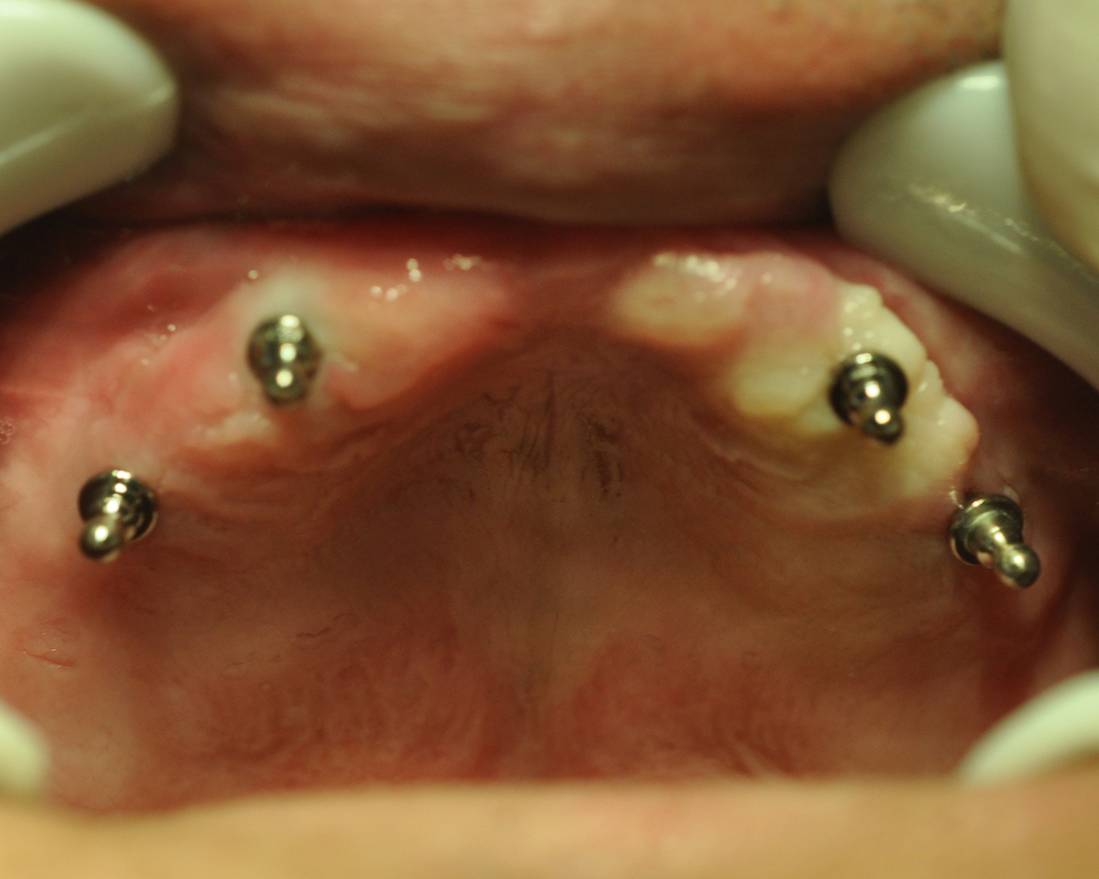

全口种植的操作程序及方法

1、修复前的常规检查:剩余牙槽嵴和颌骨的吸收程度、质量和密度的检查;咬颌记录;确定种植体数目和位置,制作模板;选择种植体;选择设计附着体固位形式:基桩外固位,螺栓固位。

2、常规种植手术和基桩连接术。